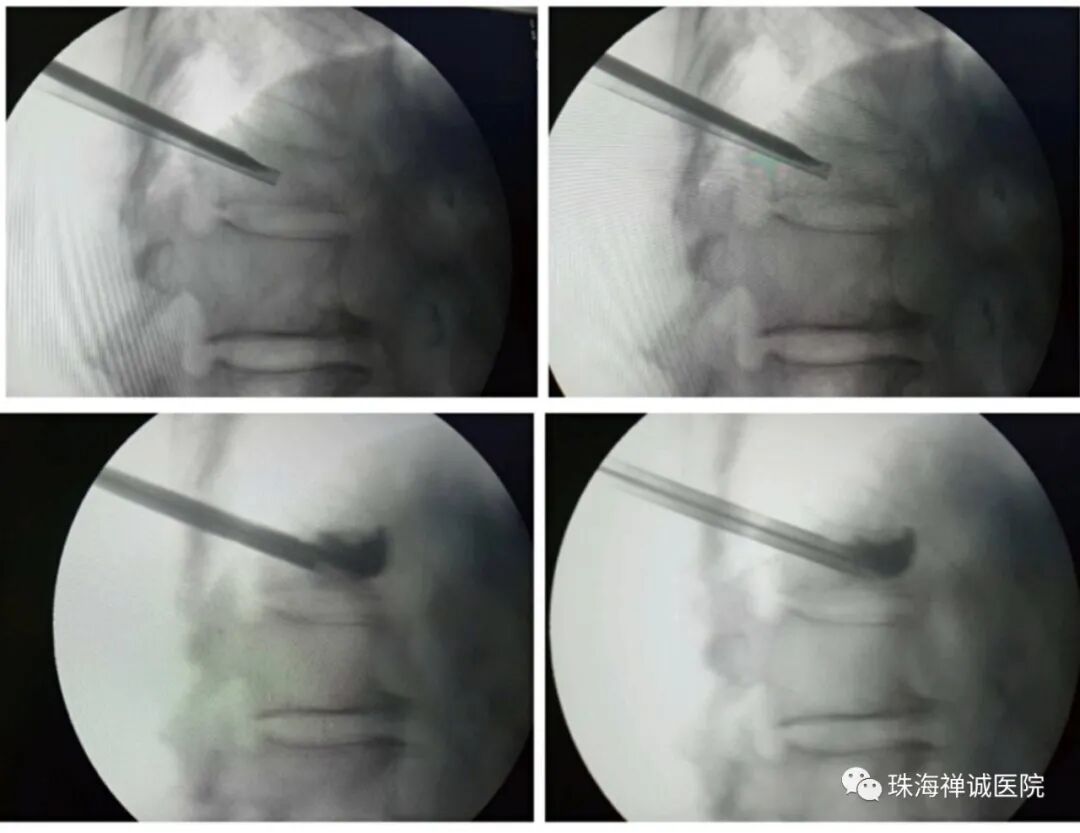

脊柱外科黄凯院长接诊后,为李奶奶做了详细的检查,最后专家团队经过术前讨论,为李奶奶制定了适合的手术方案 —— T9、L1椎体成形术。与家属详细沟通病情及治疗方案后家属同意手术。

手术当天,在黄院长带领下完美完成该手术, 整个手术过程一个小时不到,术后腰痛即刻缓解,第二天李奶奶即可下床活动,患者及家属洋溢满意笑容。

经皮椎体成形术是指经皮通过椎弓根或椎弓根外向椎体内注入骨水泥以达到增加椎体强度和稳定性,防止塌陷,缓解疼痛,使患者早期下床活动,恢复日常生活为目的一种微创脊椎外科技术。